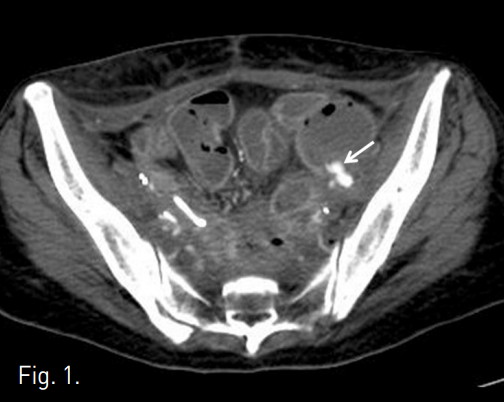

조영증강 골반 CT에서 양측 후복막에 복막전이가 있으며, 좌측 외장골동맥에서 급성출혈을 시사하는 조영제의 혈관외유출이 관찰되었다. 외장골동맥은 저혈량증(hypovolemia)으로 인하여 매우 좁아져 있었다(Fig. 1).

Fig. 1

Contrast enhanced pelvic CT shows a pseudoaneurysm (arrow) from the left external iliac artery.